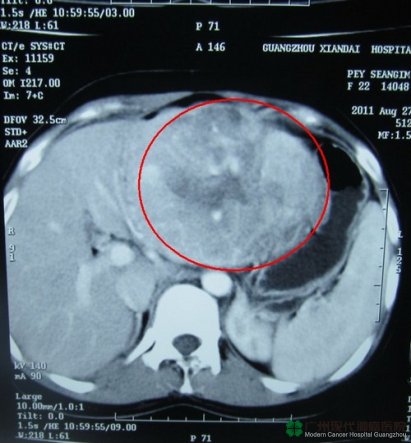

หลังจากที่เธอเข้าพักรักษาตัวที่โรงพยาบาล ก็ได้ทำ CT Scan ผลที่ได้พบว่า กลีบซ้ายของตับมีการเปลี่ยนแปลงเป็นก้อนเนื้อร้าย บริเวณระหว่างตับกับกระเพาะมีก้อนเนื้อขนาด 8 × 11 × 14 CM ต่อมน้ำเหลืองหลังเยื่อบุช่องท้องบวม กลางกลีบปอดขวาใต้หน้าอกมีจุดเล็กๆ จึงถูกวินิจฉัยว่าเป็นมะเร็งตับปฐมภูมิ ( มะเร็งตับที่เกิดขึ้นในตับเอง )

มะเร็งตับมีขนาดใหญ่ถึง 8 × 11 × 14 cm